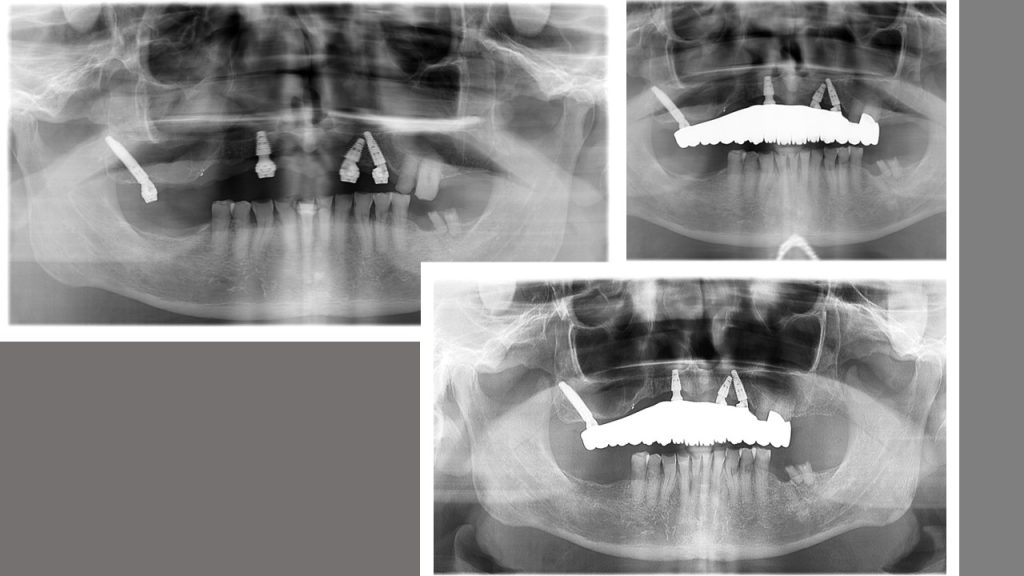

Pterygoid implant was used as there was no other option. The long span of restoration is a risk, but remains stable.

Another rescue situation showing a stable restoration over time in spite its long span